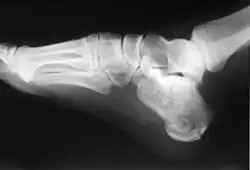

Das Fersenbein (lateinisch Calcaneus, eingedeutscht auch Kalkaneus) ist ein kurzer Knochen der Fußwurzel. Es ist der größte und längste Fußwurzelknochen und zugleich der Knochen mit dem relativ größten Anteil Knochenmark (spongiösen Knochens).

Der Körper des Fersenbeines ist grob quaderförmig. Unter der Malleolengabel des Sprunggelenkes liegt er nicht mittig, sondern zur Seite versetzt. Der Körper verläuft vom hinteren Ende des Fußes nach vorne–oben–zur Außenseite.

Am hinteren Ende befindet sich der Fersenhöcker (Tuber calcanei), der die Ferse (Calx) des Fußes bildet. Hier setzen über die Achillessehne (Tendo calcanei) der Zwillingswadenmuskel und Schollenmuskel an. Zwischen Achillessehne und Fersenhöcker liegt ein Schleimbeutel, die Bursa tendinis calcanei. Auf der Unterseite des Fersenhöckers befinden sich zwei nach vorne gerichtete Fortsätze, der Processus medialis tuberis calcanei und der Processus lateralis tuberis calcanei. Hier haben der Musculus abductor hallucis, der Musculus flexor digitorum brevis und der Musculus abductor digiti minimi ihre Ursprünge. Die Aponeurosis plantaris hat im Bereich des Fersenhöckers ebenfalls ihren Ursprung. Vom Processus medialis geht häufig der Fersensporn aus. Der Fersensporn ist eine krankhafte und schmerzhafte dornartige Verknöcherung im Ursprungsbereich der Aponeurosis plantaris.

Nach vorne hin befindet sich der Processus anterior calcanei. Hier befindet sich die Gelenkfläche für das Würfelbein, die als Facies articularis cuboidea bezeichnet wird und zusammen mit dem Würfelbein das Kalkaneokuboidgelenk bildet.

Auf der medialen Fläche des Fersenbeines befindet sich ein Vorsprung, der die Fläche „überdacht“. Dieser Vorsprung wird als Sustentaculum tali bezeichnet. Große Teile des Sprungbeines ruhen auf diesem Vorsprung. Unter dem Sustentaculum tali läuft die Sehne des Musculus flexor hallucis longus hindurch. Der Muskel erhält dadurch die Wirkung, das Fersenbein am Einknicken nach innen zu hindern. Daneben verlaufen aber auch noch die Sehnen des Musculus flexor digitorum longus und des Musculus tibialis posterior in diesem Bereich, ebenso wie Blutgefäße und Nerven. Dieser Raum wird als Tarsaltunnel bezeichnet.

Auf der oberen (dorsalen) Seite befinden sich drei Gelenkflächen:

- Facies articularis talaris anterior

- Facies articularis talaris media (diese befindet sich auf dem Sustentaculum tali)

- Facies articularis talaris posterior

Zwischen den beiden letztgenannten Gelenkflächen liegt der Sulcus calcanei, der zusammen mit dem Sulcus talaris des Sprungbeines einen als Canalis tarsi bezeichneten Tunnel bildet. Die Facies articularis talaris anterior und die Facies articularis talaris media sind gemeinsam ein Bestandteil des vorderen unteren Sprunggelenkes. Die Facies articularis talaris posterior ist Bestandteil des hinteren unteren Sprunggelenkes.

Auf der Seitenfläche befindet sich ein kleiner Höcker, die Trochlea fibularis. Dieser Höcker trennt die Sehnen des langen und kurzen Wadenbeinmuskels voneinander.